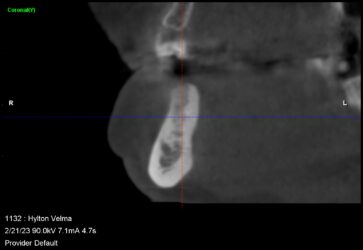

Hey guys just wanted to get to know your thoughts on what I can do to improve. This is a 78 yr old patient with controlled diabetes/hypothyroid/high BP. She takes her medications regularly and reports to be controlled. #29 was extracted due to fracture in October 2022 with bone graft. Implant Astra Osseospeed EV size 3.6×9 was placed in…

I created a deeper osteotomy today and placed a larger longer implant after removing the failed implant and thoroughly curetting and irrigating with CHX. Any guidance and feedback is welcome.